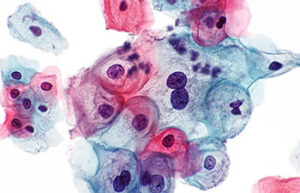

- Surgery and biopsy

- Create and induce a variety of animal models